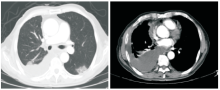

郑明英:患者在2014-10-24复查PET-CT示右肺动脉栓塞, 见图3; 放疗过程中出现频繁的恶心、呕吐, 伴咳嗽、咳痰, 查体:右下肺呼吸音减低, 11月28日复查胸部CT示:右侧胸腔积液较前增多, 左下肺出现斑片影; 胸腔积液找到腺癌细胞, 见图4。2014-11-28至2014-12-04 予抗感染治疗:头孢哌酮/舒巴坦 2.25g q8h, 2014-12-04复查胸部CT示左下肺斑片影无明显改变, 见图5; 请放射科医生重新评估胸部CT发现左肺动脉栓塞, 左下肺斑片影考虑肺栓塞造成。2014-12-12予患者GC方案化疗。

涂海燕:本患者有两处值得临床医生关注:(1)患者术后2个月CT复查即发现右侧少量胸腔积液, 术后5个月PET-CT发现右侧胸腔积液略增多, 右侧肺动脉分支栓塞。右侧胸腔积液的原因可考虑为术后改变, 肺栓塞导致右侧胸膜浆液性渗出和肺癌胸膜转移。该病例术后仅5个月, 经过诊断性穿刺确诊为肿瘤转移, 提醒临床医生在术后胸腔积液吸收不佳时应当积极确诊胸水的性质。(2)患者虽然有咳嗽咯痰的症状, 但对于恶性肿瘤合并肺栓塞, 无论是否有抗凝治疗, 新出现以胸膜为基底的实变影, 除了肺部感染外应考虑到新出现的肺动脉栓塞导致的肺梗死。